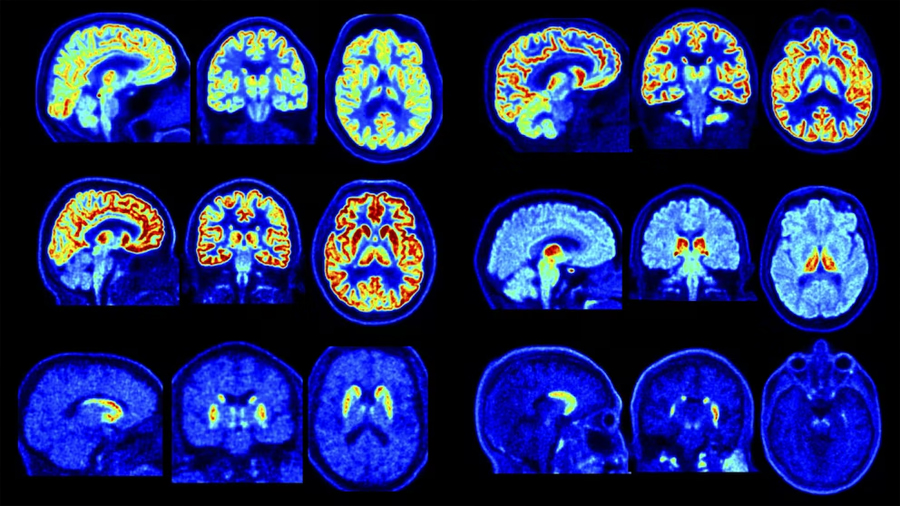

Un equipo de investigadores de la Universidad de Yale dio a conocer los primeros resultados de las pruebas realizadas con NeuroEXPLORER, un escáner cerebral de última generación que promete cambiar la forma de estudiar el cerebro humano. El dispositivo, que ya opera en el PET Center de la universidad, en New Haven (Estados Unidos), ofrece imágenes de una nitidez inédita para la investigación neurológica.

El nuevo escáner destaca porque capta señales más pequeñas, ve mejor las estructuras profundas y muestra cómo trabajan distintas partes del cerebro. Además, puede distinguir entre problemas diferentes, como tumores o daños por enfermedades como el Alzheimer y el Parkinson.

Según Tommaso Volpi, otro de los investigadores, el grupo estudió los cerebros de siete personas usando siete tipos de sustancias distintas con el escáner. Así pudieron ver claramente partes difíciles de detectar, como el tracto mamilotalámico y la sustancia negra, dos zonas clave para la memoria, el movimiento y enfermedades como el Parkinson.